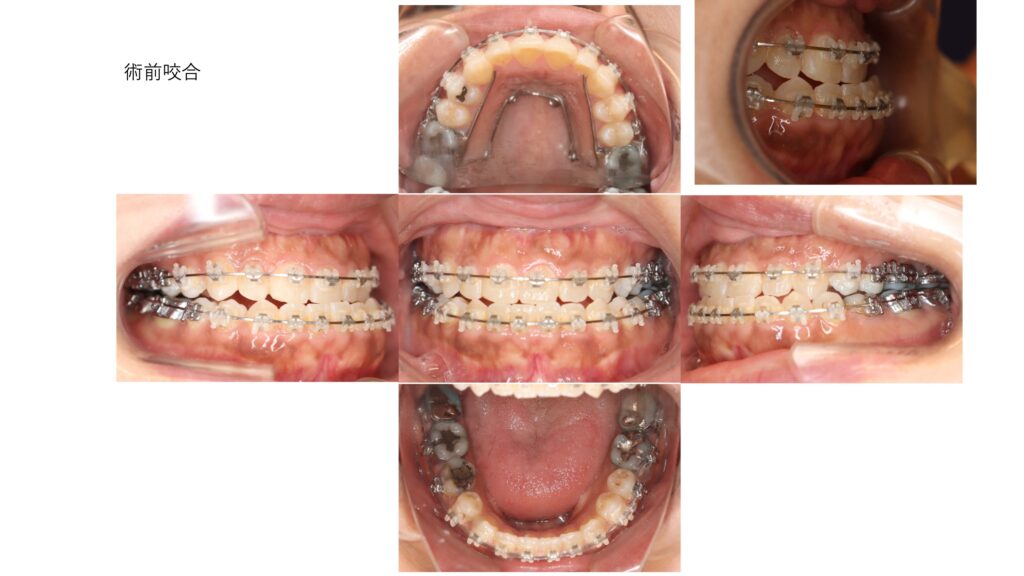

お顔を拝見すると下顎前突を認め、中顔面はやや陥没したconcave faceです。術前矯正が進み、反対咬合がはっきりとわかります。

下顎前突は解消されました。側貌では上唇のほうが下唇よりも前方に出てきて、正常な上口唇と下口唇の関係に変化しました。反対咬合は正常咬合になり、緊密な咬合関係が維持されています。